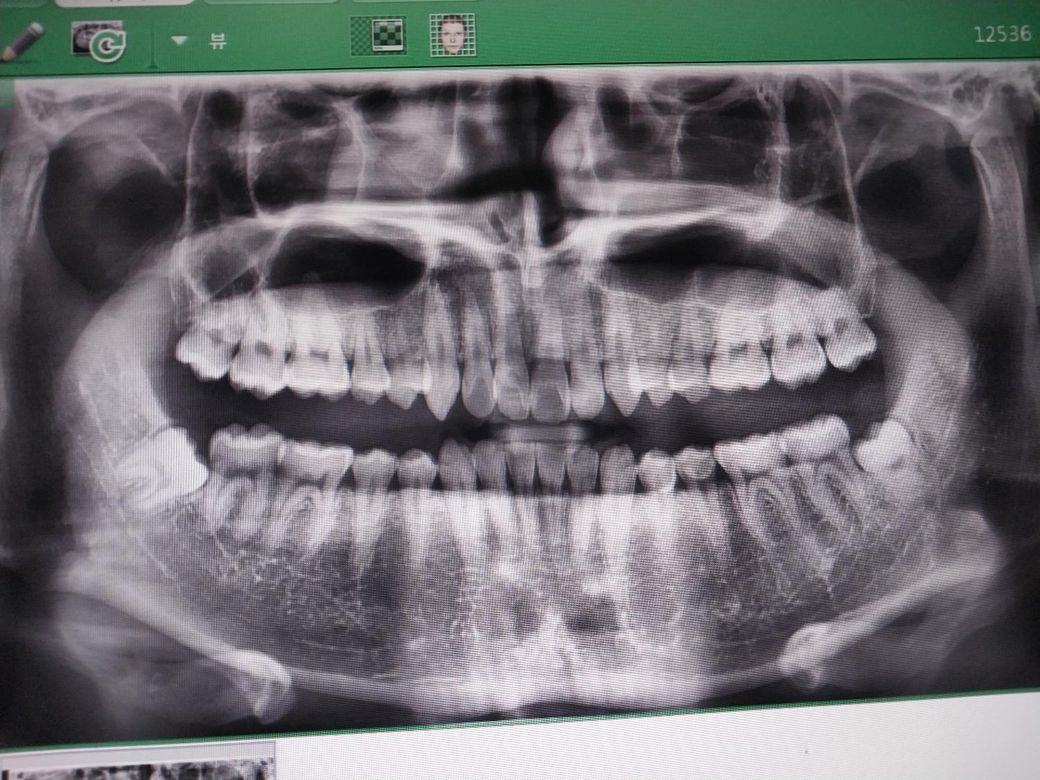

안녕하세요 제 사랑니인데 빼기 힘든 구조인가요?

왼쪽밑 사랑니는 대학병원 가야된다네요 신경이 밑으로 지나간다고 하는데 이게 거의다 자란상태라 좀 더 올라오는 일은 드물거라고도 합니다

발치가 어려운 케이스는 아니지만 치아가 신경과 가깝기 때문에 대학병원에서 발치를 하시는게 좋을것같습니다.

아래턱 사랑니의 경우 아래턱의 큰 신경관과 근접할 경우 발치 중, 후 신경손상이 있을 수 있습니다. 그래서 보통 대학병원의 구강외과로 가라고 합니다.

질문자분의 아래 사랑니는 신경관과 거의 붙어있습니다.